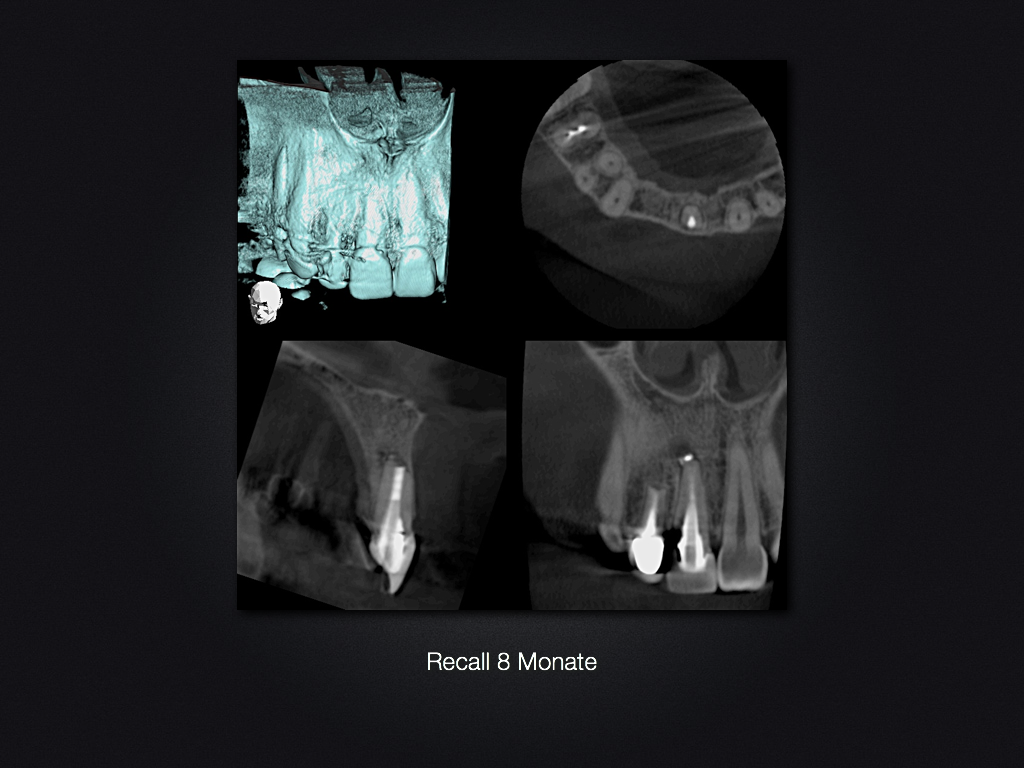

Und es heilt doch!